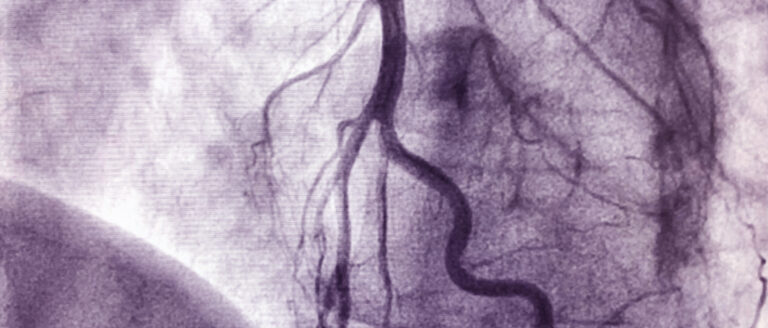

Periphere arterielle Verschlusskrankheit: wenn die Körperarterien zunehmend verstopfen

Die periphere arterielle Verschlusskrankheit (pAVK) ist eine krankhafte Verengung der Schlagadern der Beine, in seltenen Fällen auch der Arme, die zu...